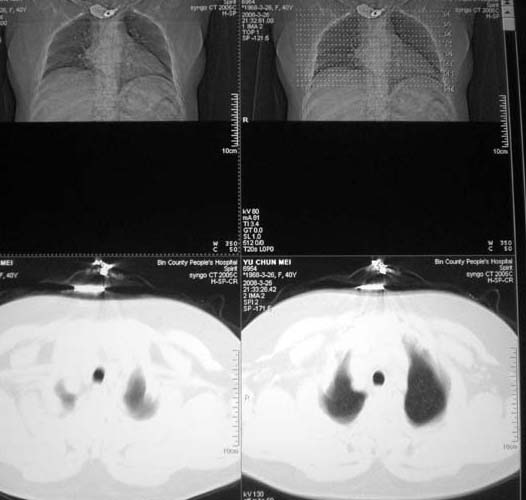

以下是引用doc张在2008-3-27 9:20:00的发言:[br]可见小叶中心型肺气肿.

以下是引用有风的日子在2008-3-27 16:59:00的发言:[br]片子上的信息与提供资料有矛盾点:到底是40岁还是56岁?[br]双下肺野可见散在、大小不等的无壁高透过影,支持小叶中心性肺气肿诊断[br]女同志有80%的症状与情绪有关,有能全靠疾病解释